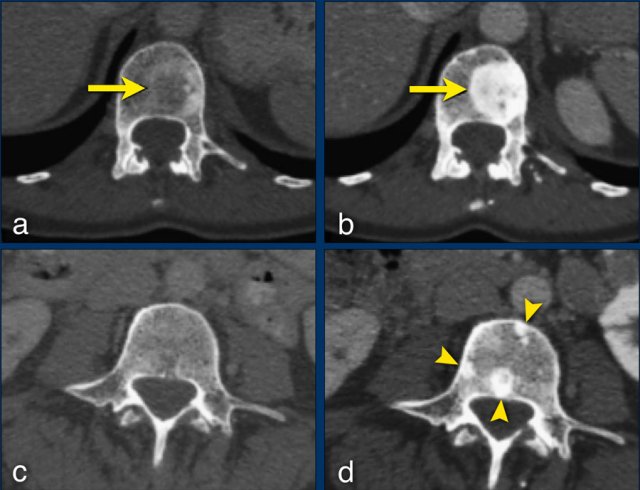

Any new lesion means progressive disease, but not every newly detected lesion is always a true new lesion.

In osteolytic bone metastases it can be difficult to determine if a sclerotic lesion that is detecting during follow up is truly a new lesion.

The CT images are of a 50-year-old female with bone metastases of a breast carcinoma.

At baseline (a), there is an osteolytic lesion in a thoracic vertebral body (arrow).

After chemotherapy, the thoracic osseous lesion has not changed in size, but has become completely osteoblastic (arrow in b), representing a good response.

In the lumbar vertebra no visible metastases were seen in the baseline scan (c).

The ‘new’ sclerotic lesions in the lumbar vertebra (arrowheads in d), are considered to be small osteolytic metastases that the baseline CT failed to identify.

They became visible due to the osteoblastic reaction.